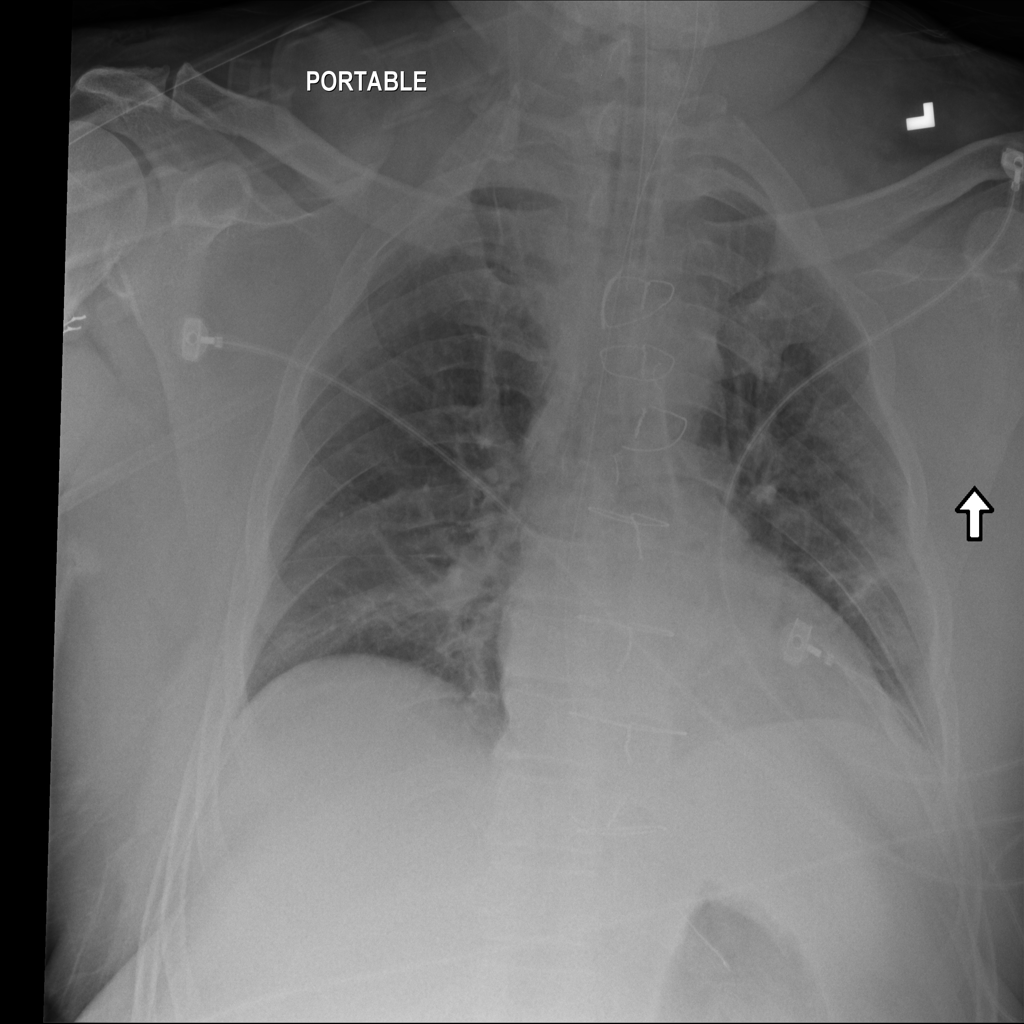

PAT-BB06 · IMG-001Atelectasis

PAT-BB06 · IMG-001

PA